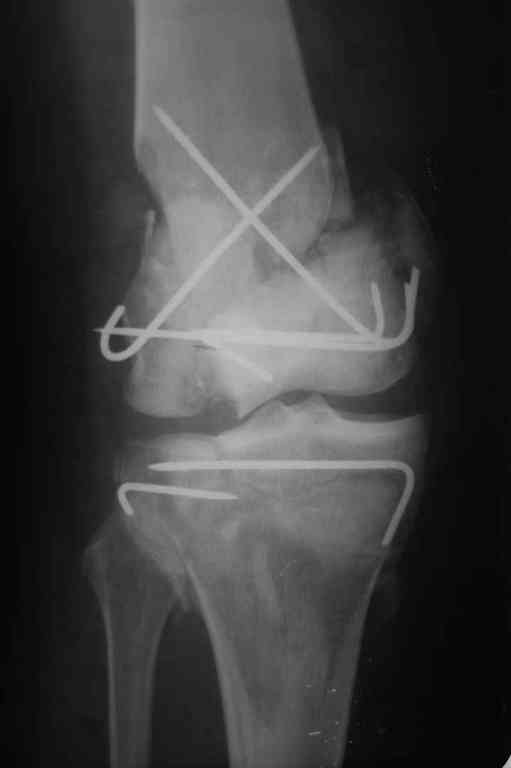

Re: Последствия открытого перелома дистального отдела бедра

Коллеги фиксатор Numelock II